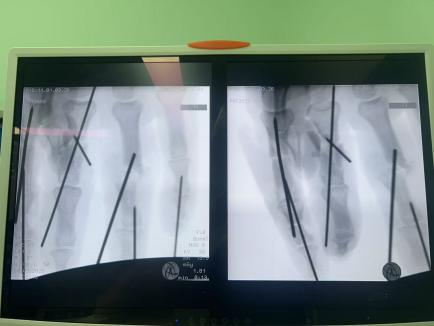

骨折內(nèi)固定+肌腱神經(jīng)修復:不僅要讓手指“活”,更要讓手指“能用”。

面對這些困難,許攀峰團隊沒有卻步,沉著應戰(zhàn)。他們先是為骨折的手指進行精準內(nèi)固定,重建骨骼支撐;隨后,在顯微鏡下,一根根尋找斷裂的血管、神經(jīng)和肌腱——清創(chuàng)、修剪、吻合、通血……每一步都如履薄冰,每一次打結都需屏息凝神,手術室內(nèi),寂靜無聲,只有時鐘的滴答聲在空氣中回蕩,仿佛在為這場生命的接力默默計時。

1小時、2小時、3小時…… 時間在寂靜中流逝,顯微鏡下,一雙雙手在無聲地忙碌著,他們的動作嫻熟而精準,如同在跳一場無聲的生命舞蹈。終于,將近5個小時后,最后一針縫線完成。松開止血鉗,所有再植的手指瞬間恢復紅潤,指腹飽滿,毛細血管反應靈敏——手術成功了!這一刻,手術室內(nèi)壓抑的氣氛瞬間被打破,許攀峰團隊成員們臉上露出了欣慰的笑容。